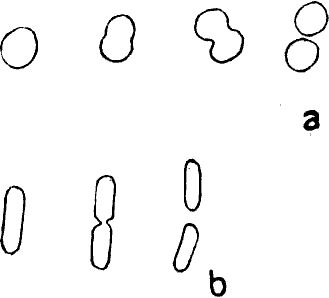

Ein halbes Jahrhundert später erst gelang es den geschickten Händen Antony van Leeuwenhoeks, kleine Linsen so sorgfältig und gleichmäßig zu schleifen, daß sie alle bis dahin angefertigten an Vergrößerungskraft übertrafen; er vervollkommnete hierdurch und durch kleine anderweitige Kunstgriffe seine optische Ausrüstung in bisher noch nicht dagewesenem Maße und untersuchte nun – von Haus aus ohne jede naturwissenschaftliche Ausbildung – mit ihrer Hilfe allerhand Flüssigkeiten: Regenwasser, Pflanzenaufgüsse, Darminhalt von Tieren und Menschen, den eigenen Speichel u. a. m. mikroskopisch.[3] Überall fand er – bald reichlicher, bald spärlicher – kleinste, vollkommen farblose »Tierchen«, die verschieden gestaltet, zum Teil lebhaft beweglich waren. Dank einer vorzüglichen Beobachtungsgabe und ebenso großer Zuverlässigkeit beschrieb Leeuwenhoek diese »Tierchen« so genau, daß wir sie heute mit Sicherheit als Bakterien wiedererkennen können. Auch gab er durchaus naturgetreue Abbildungen von ihnen, die die drei Hauptformen der Spaltpilze vollkommen richtig darstellen: alle die unzähligen Bakterien, die seitdem beobachtet worden sind, lassen sich ihrer Gestalt nach in kugelförmige (Mikrokokken), stäbchenförmige (Bazillen) und schraubenförmige (Spirillen) scheiden (s. Abb. 1). Freilich wechseln sie nach Dimensionen und kleinen Einzelheiten ihres Baues, wie wir sehen werden, in mannigfaltigster Weise, aber alle lassen sich auf einen der drei schon von Leeuwenhoek unterschiedenen Grundtypen zurückführen.

Unter den Lebensvorgängen, die der unmittelbaren Beobachtung zugänglich sind, beansprucht vor allem die Art und Weise der Fortpflanzung unser Interesse. Gerade ihre zuverlässige Beobachtung ist durch die Kochsche Isolierungsmethode außerordentlich erleichtert worden, wenn auch schon vor Koch vielfach richtige Ansichten über die Art und Weise, wie die oft enorme Vermehrung[17] von Bakterien im einzelnen zustande kommt, gewonnen worden sind. Die Vermehrung der Bakterien erfolgt auf eine sehr einfach erscheinende Weise durch Spaltung. Der Mikrokokkus, das Kugelbakterium, das sich zur Teilung anschickt, zeigt eine langsame Vergrößerung einer seiner Achsen, dann eine Einschnürung in der Mitte und endlich eine vollkommene Abschnürung von zwei neuen Tochterkugeln. Ganz analog ist der Teilungsvorgang bei Stäbchen- und Schraubenbakterien, die nach anfänglichem Längenwachstum durch Querteilung in zwei Tochterindividuen zerfallen (vgl. Abb. 6).